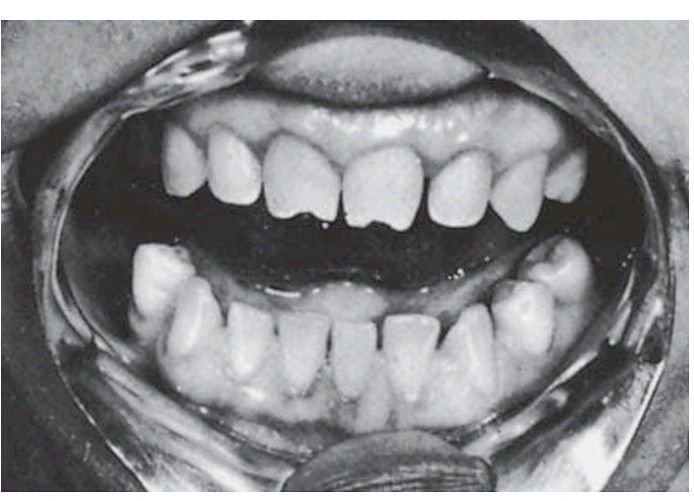

Congenital syphilis: Hutchinson’s teeth. The characteristics are the notched incisal edge and the peg shape tapering from neck to tip. (Taken before the advent of colour photography.)